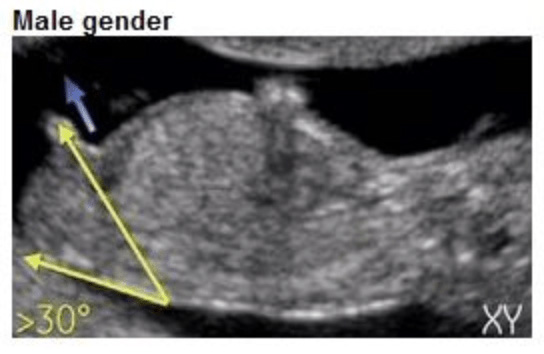

Het verschil? De hoek. Bij een jongen staat de nub in een hoek van meer dan 30 graden ten opzichte van de ruggengraat. Bij een meisje ligt de nub meer horizontaal, evenwijdig aan de ruggengraat.

• Bij een jongen: de nub begint omhoog te wijzen, in een hoek van 30 graden of meer ten opzichte van de ruggengraat. Hij groeit uit tot de penis.

• Jongen: zoek naar een nub die duidelijk omhoog wijst, in een hoek ten opzichte van de onderrug. Soms is er al een kleine verdikking zichtbaar aan het uiteinde.

Echo met nub in hoek van 30+ graden, kenmerkend voor een jongen

Nub jongen (30°+)